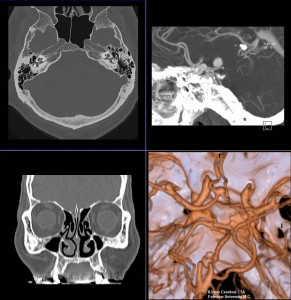

当院では、ドイツ・シーメンス社製マルチスライスCTを導入いたしました。

この装置は高速で回転し、短い時間で検査が可能な最先端マルチスライスCTで、従来の装置と比較して息を止める時間が短縮されます。また細かい情報を得ることができ、脳や腹部の血管や骨などの3D画像(立体再構成画像)を高精細に描出可能です。さらに、X線の被ばくも従来のCT装置に比べ低減されています。

頭だけではなく、全身のCTを撮ることが出来ます。